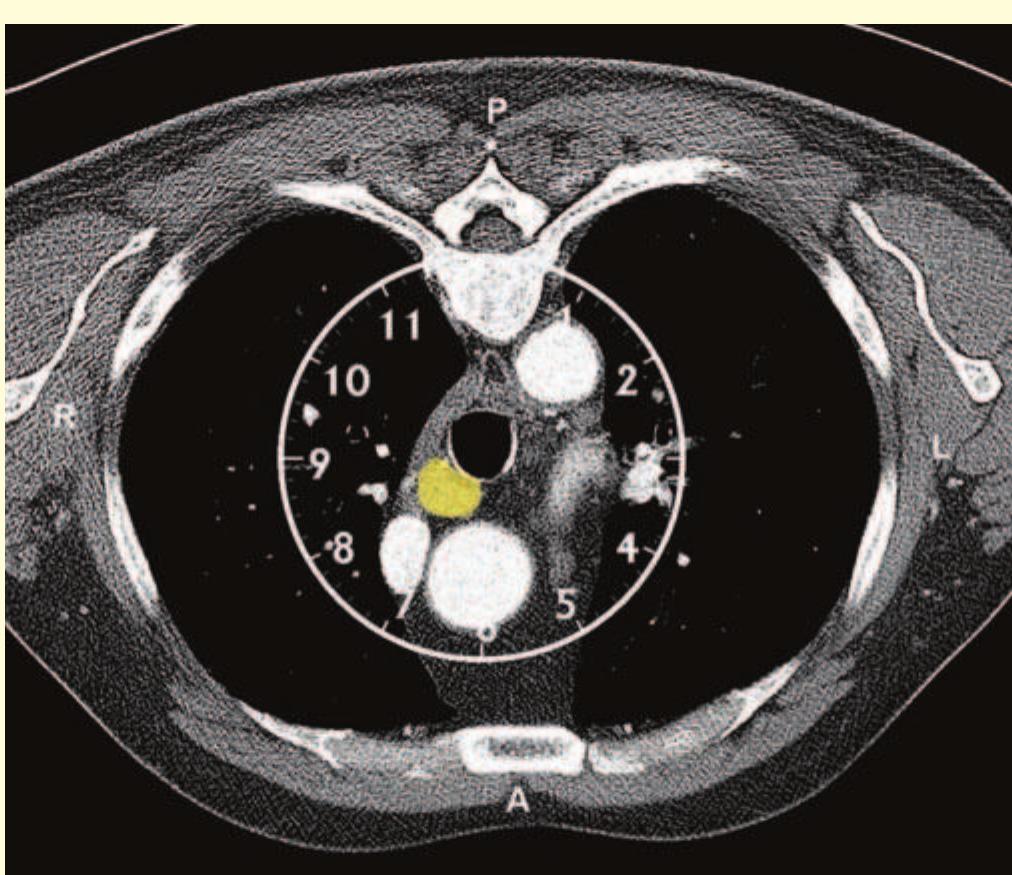

- The bronchoscope is then rotated anticlockwise by 150° to examine the subcarinal lymph nodes (station 7), extending down to the distal margin of the bronchus intermedius.